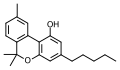

Let's start with some background on marijuana chemistry. Relevant chemicals in marijuana fall into two broad classes: cannabinoids (which in plants are specific to the Cannabis genus) and terpenoids (which are widespread in many plants).[7][8] Humans and other animals, produce endocannabinoids, which are different than but in the same chemical class as those cannabinoids found in cannabis. The main psychoactive chemical in marijuana is tetrahydrocannabinol (THC). Another important cannabinoid is cannabidiol (CBD), which is not psychoactive but has many claimed health benefits. Terpenoids in cannabis include ocimene, myrcene, β-caryophyllene, limonene, pinene, myrcene, linalool.